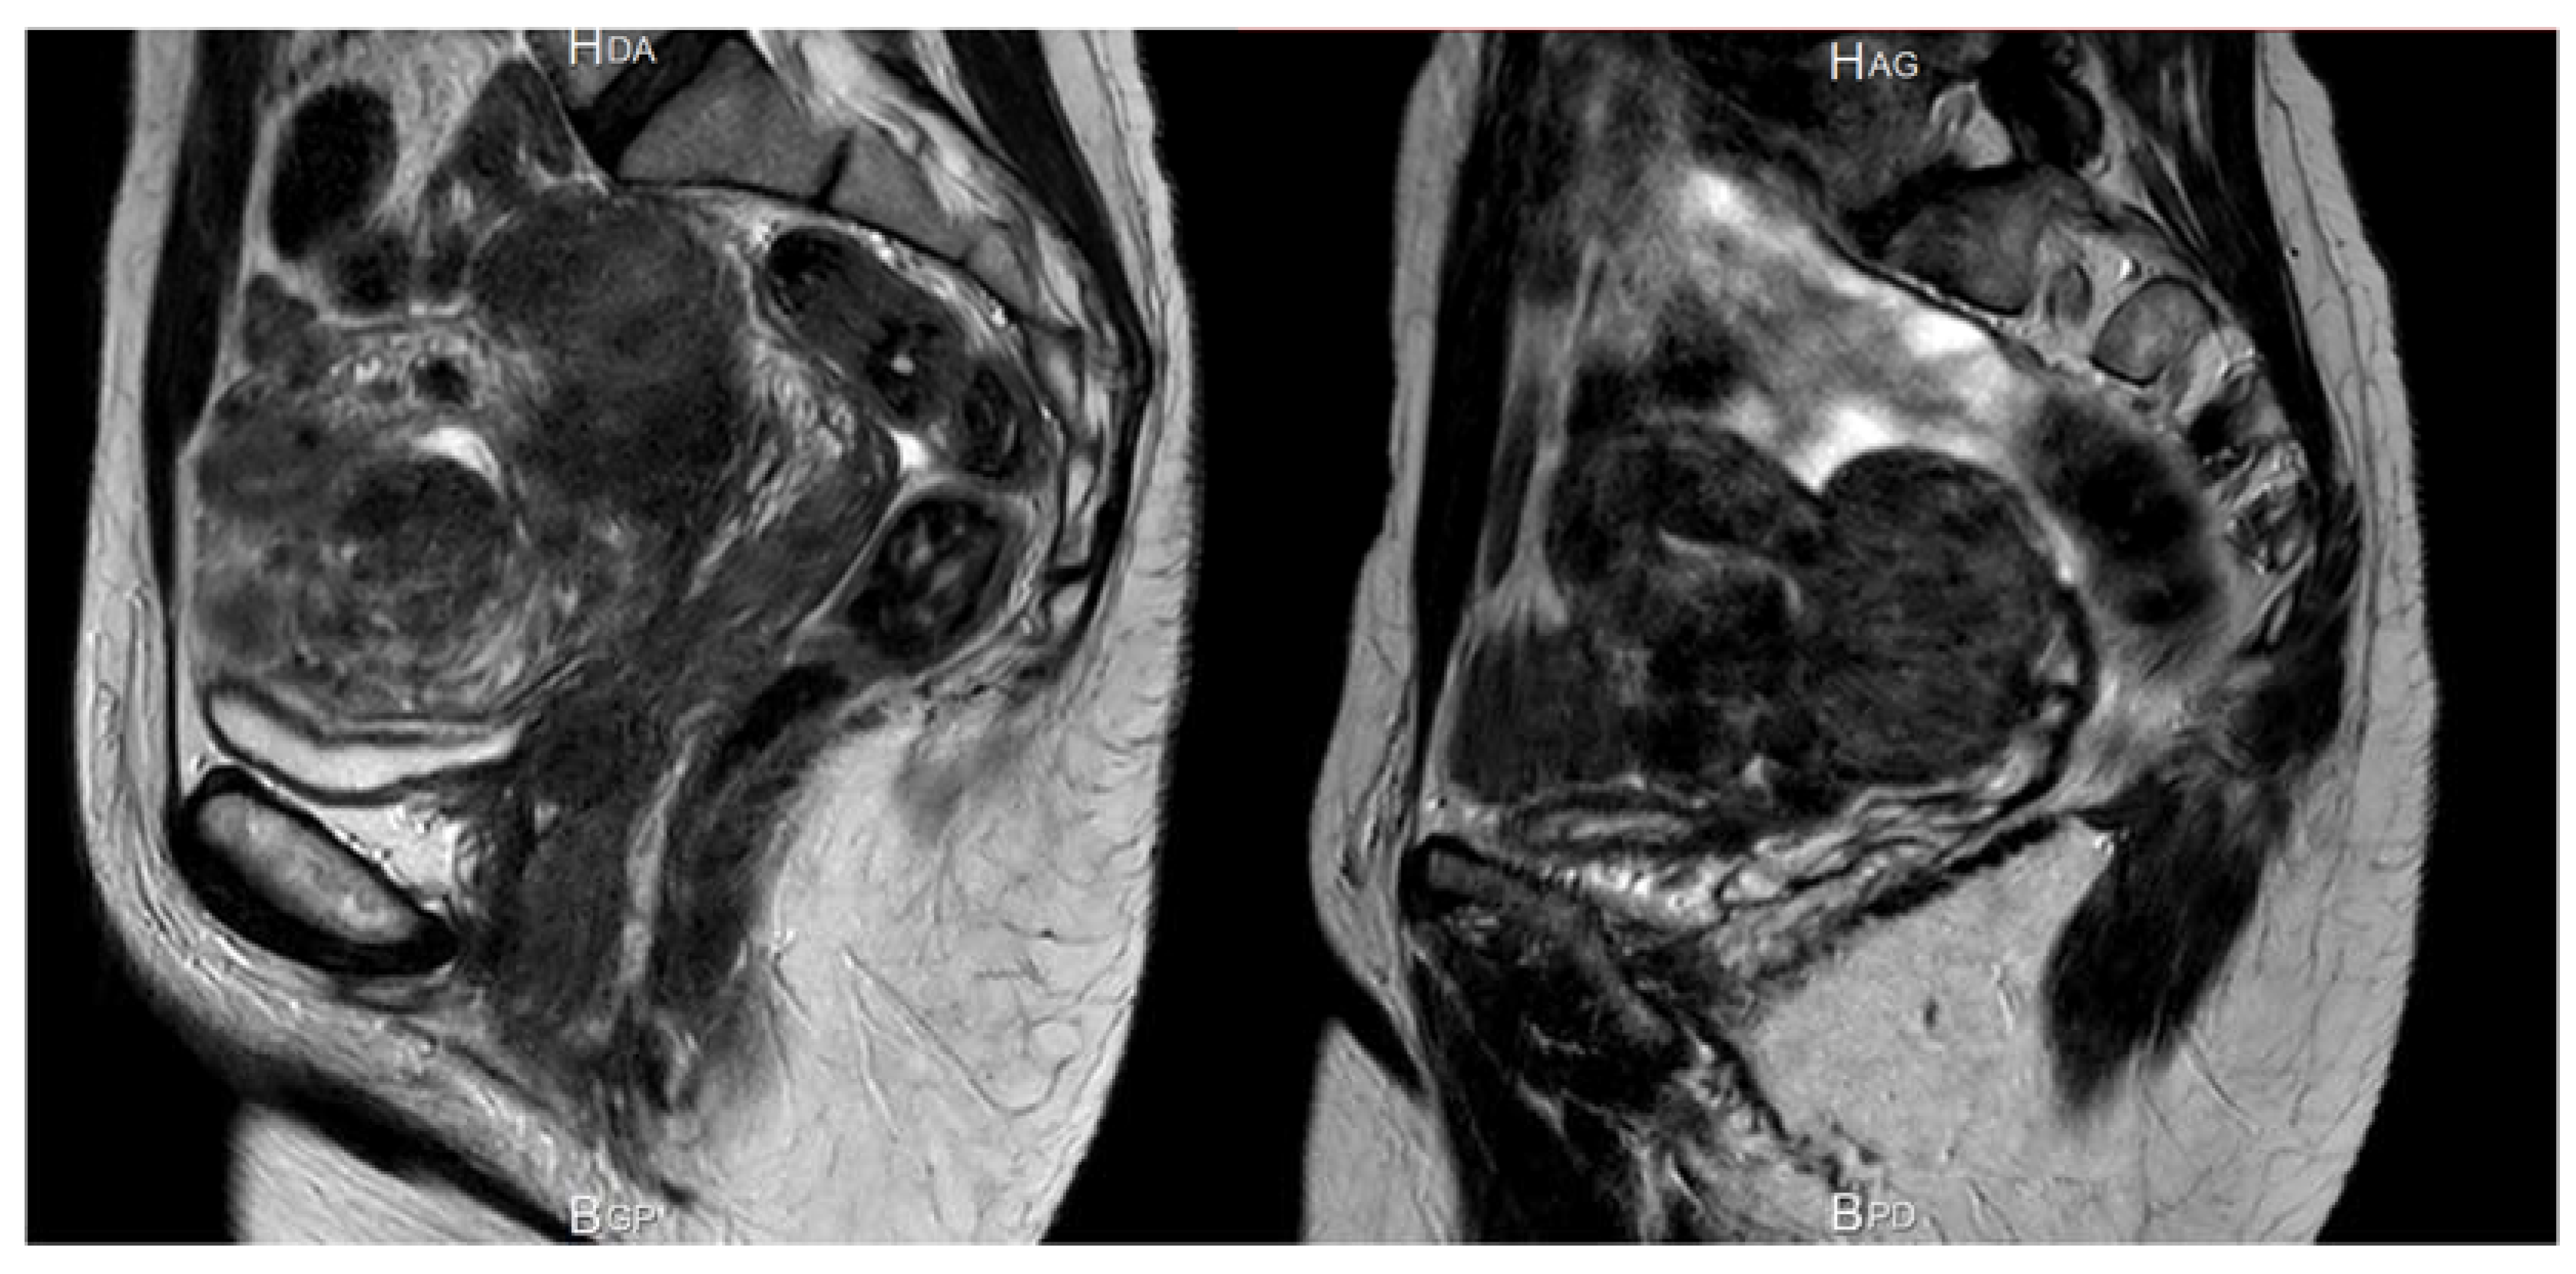

Enhanced vascularization can be seen by hysteroscopy performed at the time of menstruation [20]. Since the early 1990s, hysteroscopy has become a routine diagnostic tool, often combined with transvaginal ultrasound. During menstruation, active bleeding can be observed by pressure-controlled hysteroscopy [21] (Figure 3).

Figure 3. Enhanced vascularization with the presence of dilated blood vessels on the myoma surface, visible by hysteroscopy.